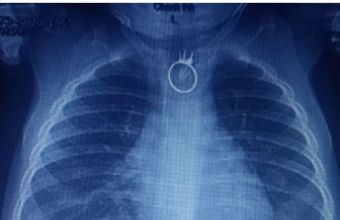

Його турбувала постійна слинотеча, з’явилися порушення дихання та задишка. Малюк не міг нічого ковтати. Тож вони одразу вирушили до місцевої лікарні у Новому Роздолі. Там лікарі зробили малюкові рентген, на якому побачили сторонній предмет. Дитину негайно каретою швидкої допомоги доставили до Центру дитячої медицини.

«Одразу після госпіталізації, о другій ночі, ми взяли дитину на операційний стіл і провели ригідну езофагоскопію з видаленням стороннього тіла. Це був перстень. Все пройшло успішно та без особливостей. Єдине, що іграшковий перстень трохи пошкодив стравохід», – розповів дитячий хірург Олександр Колодій.